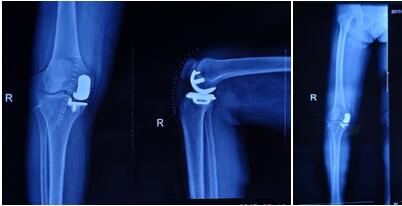

近日骨科在張富軍主任帶領(lǐng)下,在保膝理念的驅(qū)動下,成功開展我院首例生物單髁膝關(guān)節(jié)置換術(shù),更是全國第9例,西北地區(qū)第2例。這意味著本次手術(shù)在西安市內(nèi)乃至整個西北地區(qū)都極為罕見,我院在骨關(guān)節(jié)病診治技術(shù)邁上了新的臺階,為膝關(guān)節(jié)炎患者提供了一種新的選擇。

? ? ? ?提起膝關(guān)節(jié)置換術(shù),多數(shù)病人起初都是拒絕的,至少在單髁置換術(shù)出現(xiàn)之前,不乏有“談虎色變”的患者,而這些患者普遍遺留這樣一個問題:能否僅置換部分磨損的關(guān)節(jié),保留大部分自體關(guān)節(jié),用更小的創(chuàng)傷解決痛苦呢?答案是肯定的,隨著科技的進步和手術(shù)技術(shù)的精湛,單髁關(guān)節(jié)置換應(yīng)運而生,成為近2年風靡一時的手術(shù)方式,術(shù)中要求精確至1mm,其具有創(chuàng)傷小,恢復(fù)快,骨長入理想,骨質(zhì)保留量大,本體感覺不破壞的優(yōu)勢。目前膝關(guān)節(jié)單髁置換多為骨水泥型,生物型全國僅開展9例。生物型作為全新的置換方式比骨水泥型更具有突出的優(yōu)勢,逐漸成為新的趨勢。